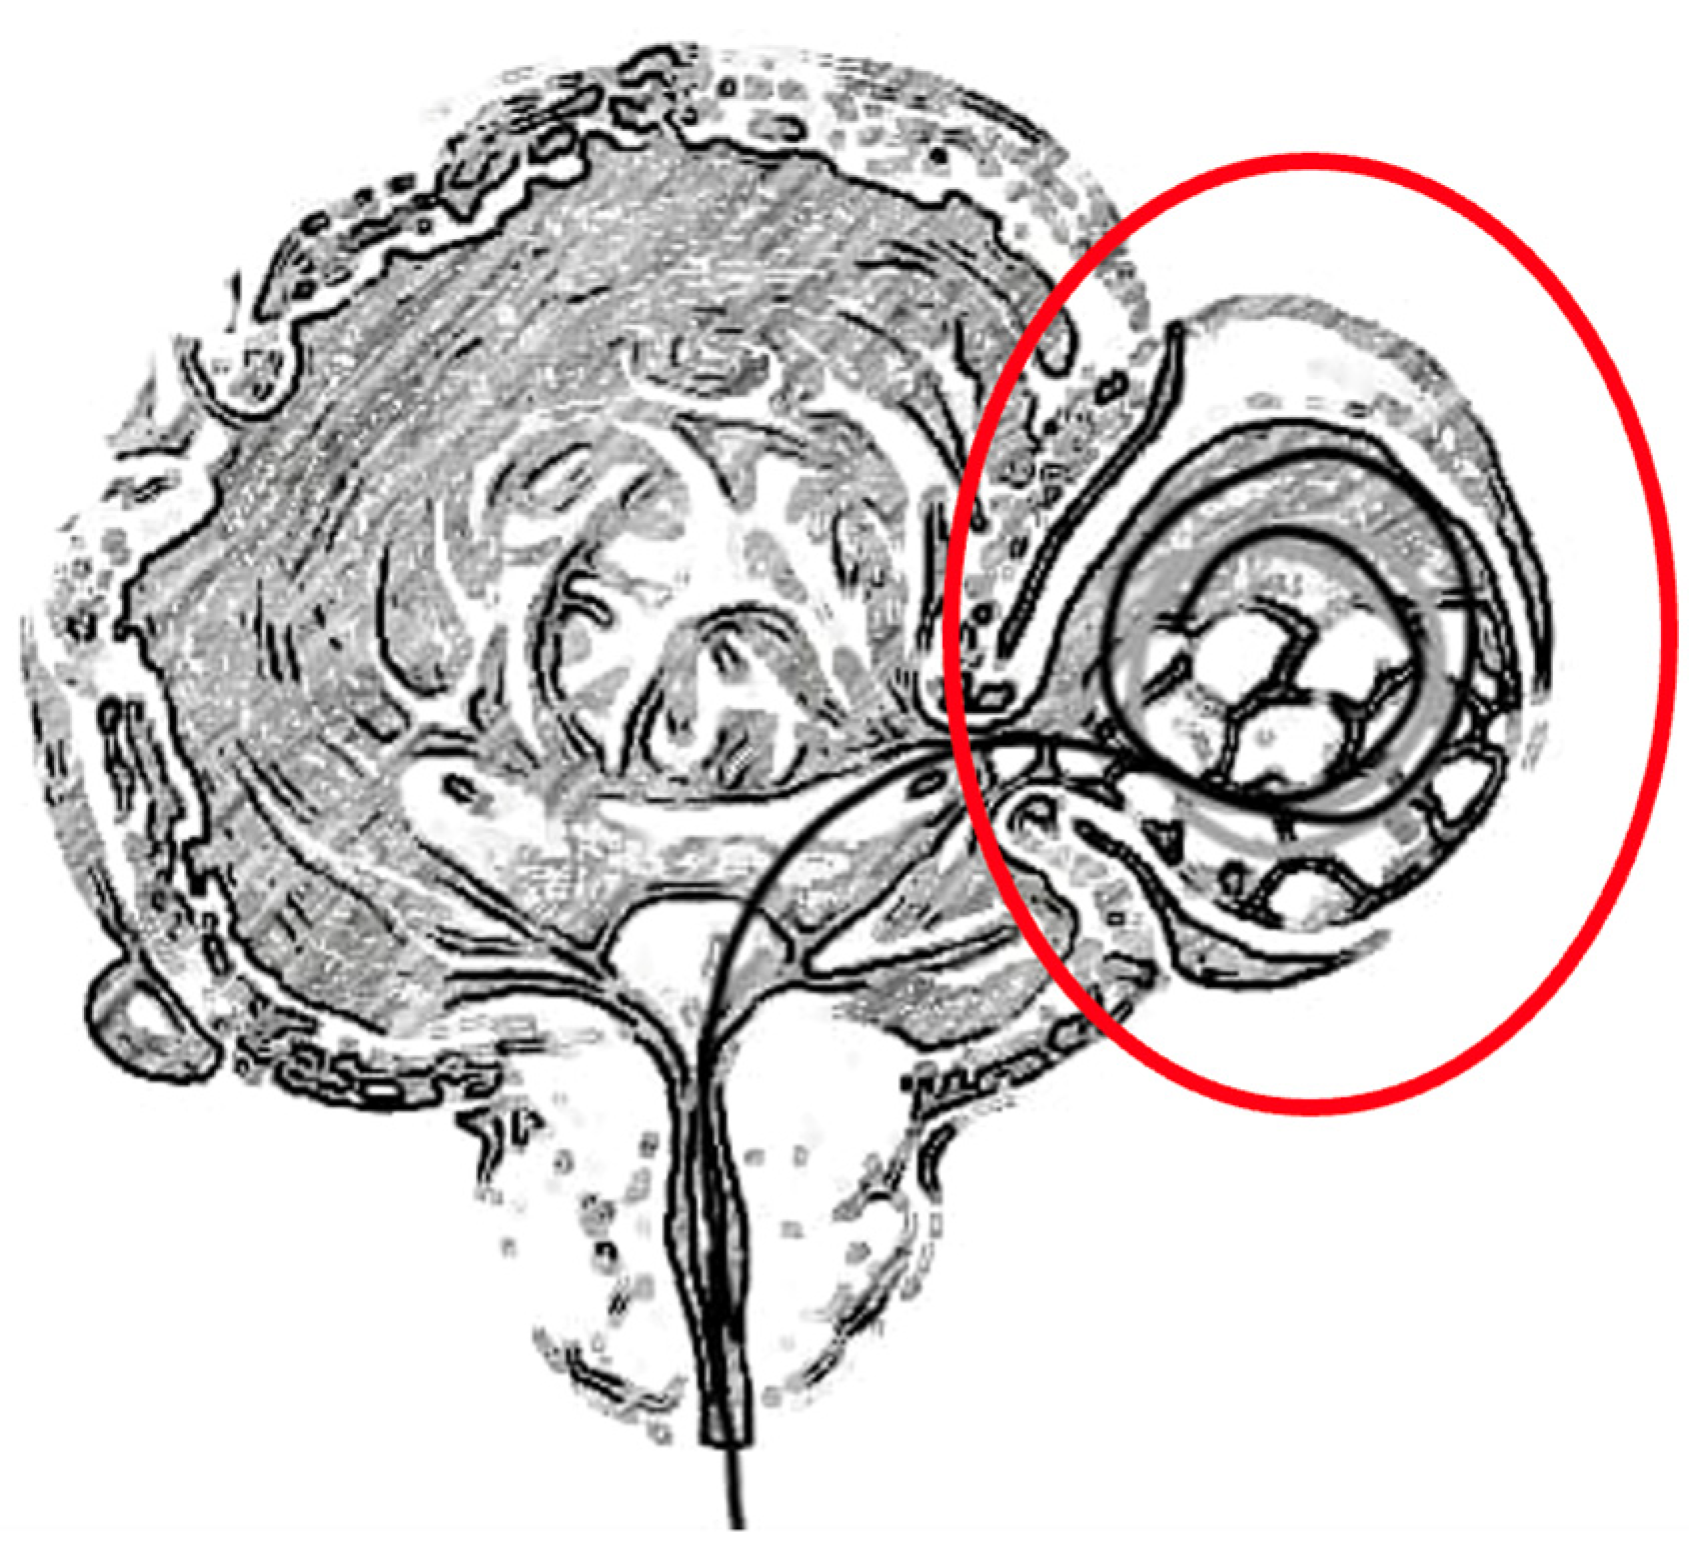

Minimally Invasive Guidewire-Aided Bladder Diverticulectomy with or Without Other Prostatic Intervention: Step by Step Description of the Procedure

3. Surgical Technique